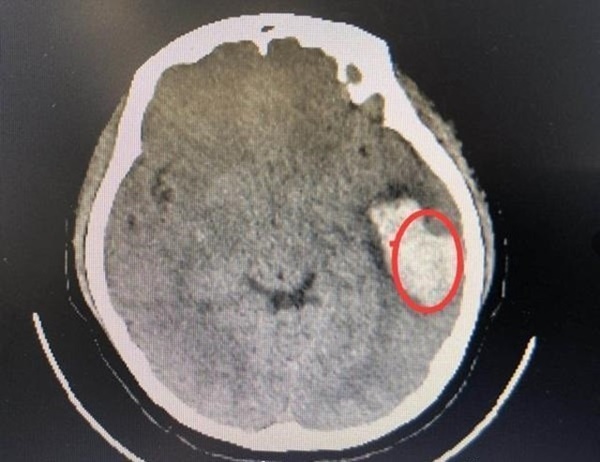

Bác sĩ Lưu Kỳ, bệnh viện The First Affiliated Hospital of Zhengzhou University, cho biết sau khi kiểm tra phát hiện bệnh nhân xuất huyết não khoảng 30ml máu. Nếu trường hợp này xảy ra ở nhóm người cao tuổi thì người bệnh có thể rơi vào trường hợp xấu là hôn mê hoặc liệt nửa người.

Xuất huyết não tự phát xảy ra trong vòng 72 tiếng là giai đoạn nguy hiểm nhất, người bệnh cần được đưa vào phòng chăm sóc đặt biệt và theo dõi chặt chẽ sự thay đổi của đồng tử. Tuy người bệnh vẫn còn trẻ nhưng tình trạng của bệnh nhân không thể xem nhẹ.